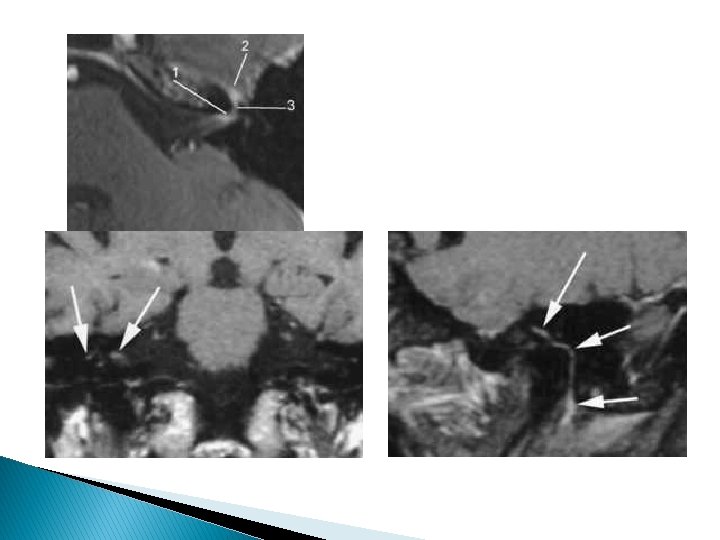

Infiltrations périneurales Tous les territoires innervés par le facial et ses branches collatérales sont à explorer lors du bilan d’une paralysie faciale persistante.

Difficulté de l’imagerie : trajet long (+++) du NF exocrânien + ses branches terminales ◦ Supérieure temporo-faciale ◦ Inférieure cervico-faciale

Les différentes anastomoses nerveuses du facial expliquent la diffusion périneurale de proche en proche pouvant en imposer pour une atteinte de la base du crâne ou une méningo-radiculite métastatique A : VII et V 2 par Nf grand pétreux (FPP) ; B : VII et V 3 par la corde du tympan et Nf petit pétreux ; C : VII et IX par l’anse de Haller (en dedans du trou stylomastoïdien ; D : VII et X (fosse jugulaire)